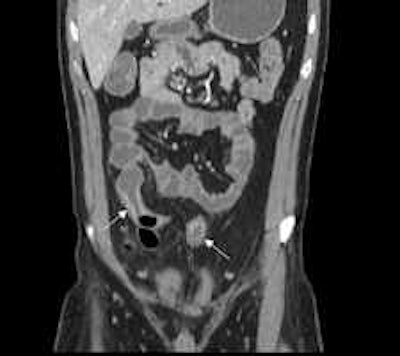

Patient with active ileocolonic Crohn\'s disease. Arrows highlight regions of hyperenhancement and thickening in small bowel depicted on coronal image acquired during CT enterography. Image courtesy of Dr. David Bruining.','dvPres', 'clsTopBtn', 'true' );" > Patient with active ileocolonic Crohn's disease

Patient with active ileocolonic Crohn's disease.